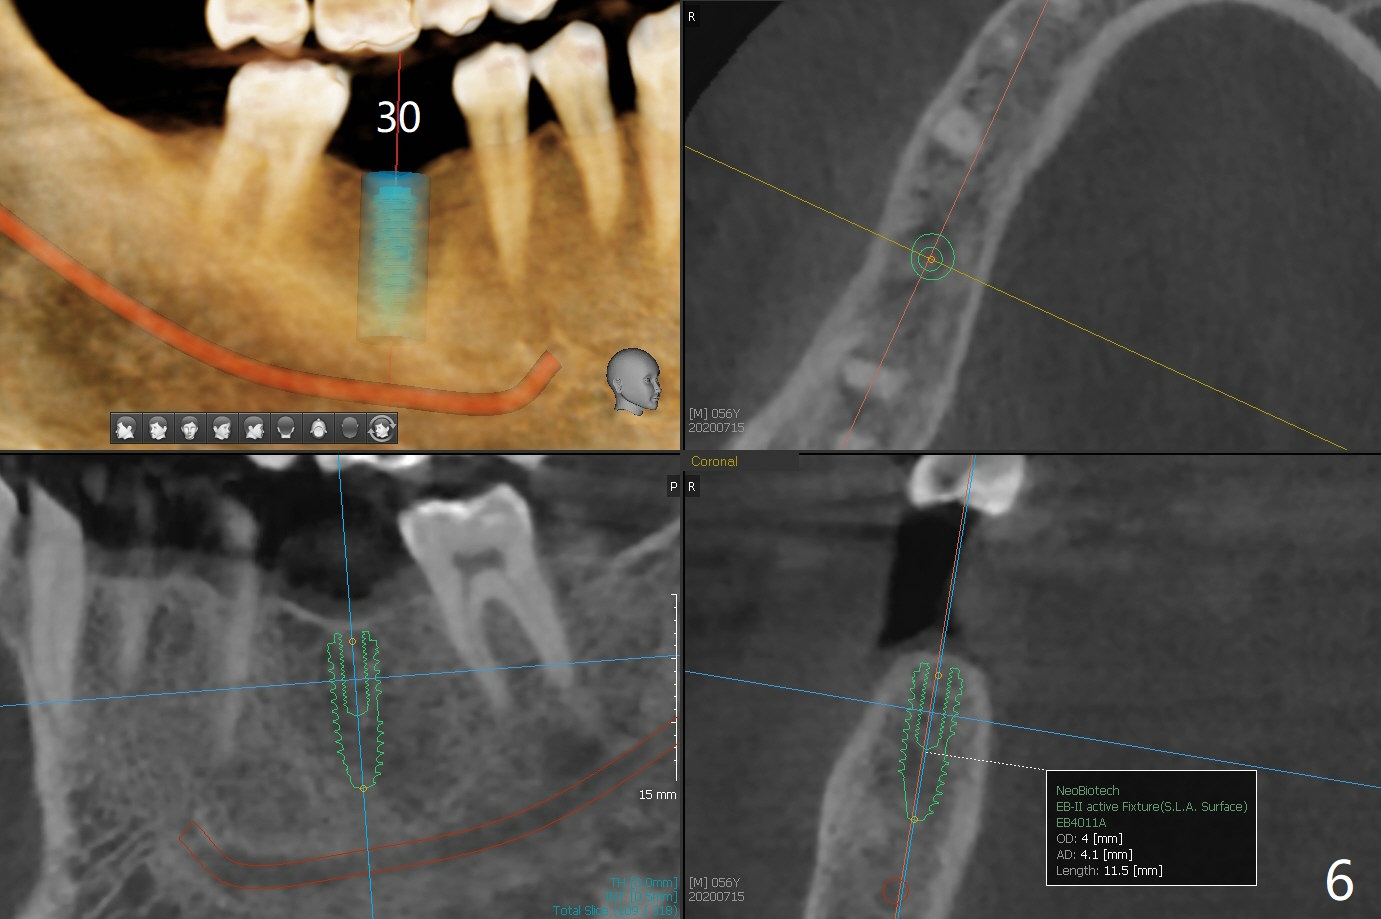

A 56-year-old man (smoker) has pain at #2 (Fig.1-3 thickened sinus membrane (R>L), C: mucous retention cyst) associated with subgingival crack (Fig.4 arrowheads). A 5x8.5 mm implant will be immediately placed with sinus lift aided by PRF membrane (Fig.5). A narrow implant will be placed at #30 (Fig.6).